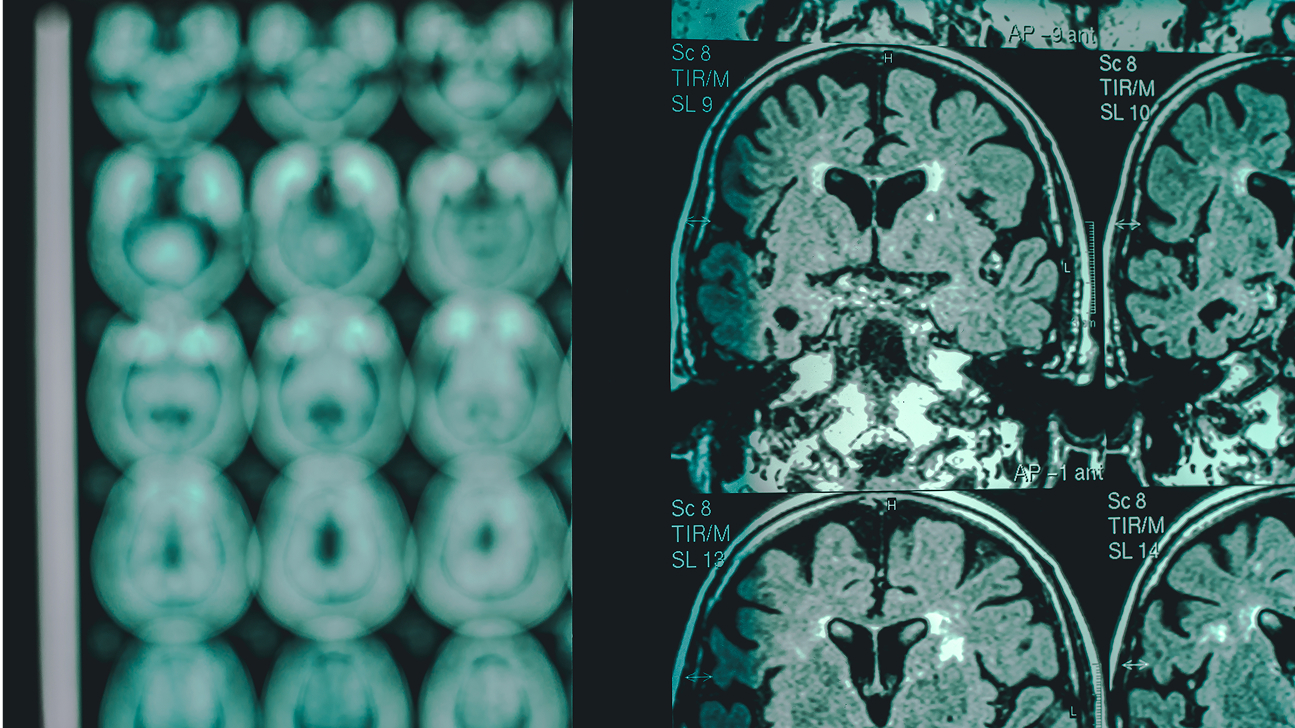

To improve the accuracy of diagnoses, Hassan and colleagues developed ClinGRAD, a multimodal heterogenous graph neural network that analyzes genomic data, magnetic resonance imaging (MRI) of the brain, and clinical information about patients, making a prediction about the type of dementia they have. The system classifies patients into four groups: healthy control, mild cognitive impairment, vascular dementia, and Alzheimer’s disease.

When analyzing MRI data, clinicians often assess bilateral differences across brain hemispheres. They also use advanced imagining techniques, including a method called diffusion-weighted imaging (DWI) that provides insights related to the progression of dementia. And when analyzing genetic data, clinicians look at what are known as gene co-expression networks, which illustrate how genes are activated together across different regions of the brain. ClinGRAD benefits from these methods.